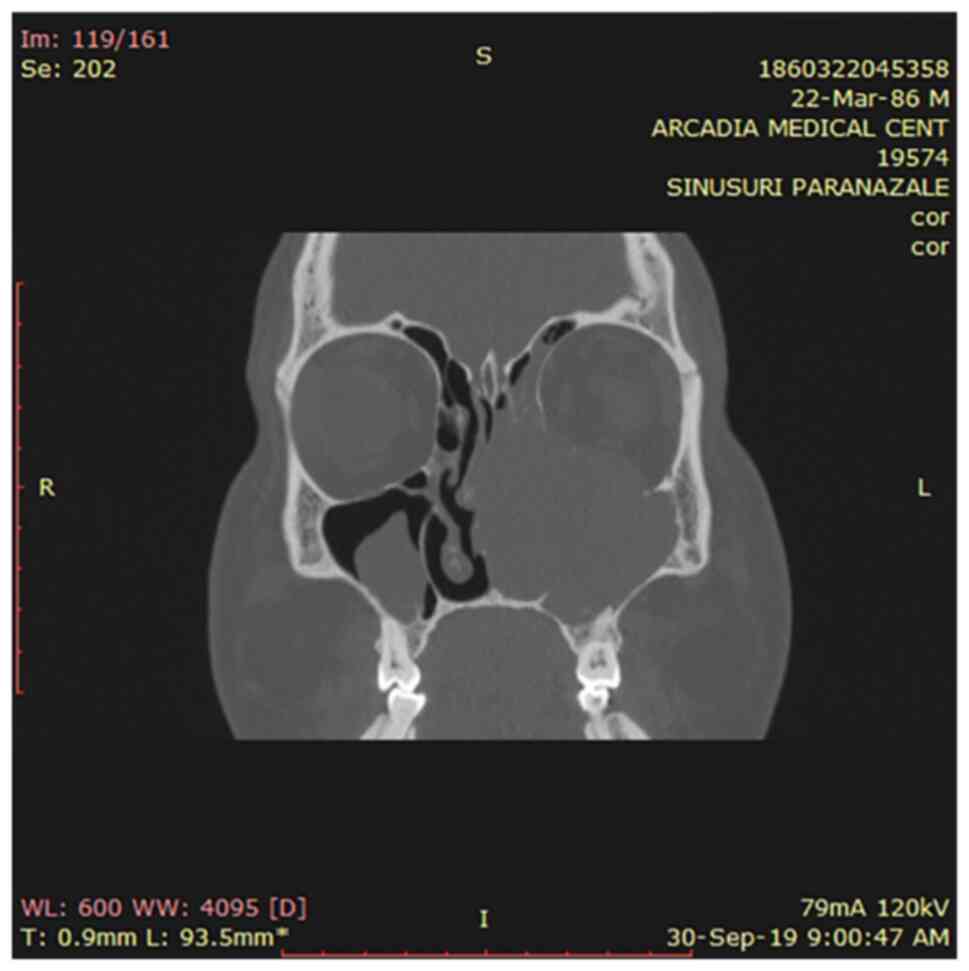

Another CT scan was performed followed by cranial MRI examination that showed a large irregular tumor mass with heterogeneous density filling the left nasal cavity and involving the left paranasal sinuses. An expansive osteolytic bone destruction pattern was observed in the ethmoid bone, medial and lateral walls of the left maxillary sinus and orbital floor. Left obstructive sinusitis and left exophthalmy were also present. The lesion was isointense on T1 weighted images and exhibited mild hypointensity on T2 weighted images (Fig. 1). There was no evidence of metastasis on the total body scan.

Figure 1

Paranasal CT prior to surgery revealed the presence of a mass in the left maxillary and ethmoidal sinuses, bone destruction of the orbital floor, nasal septum and the medial, anterior and inferior wall of the left maxillary sinus.